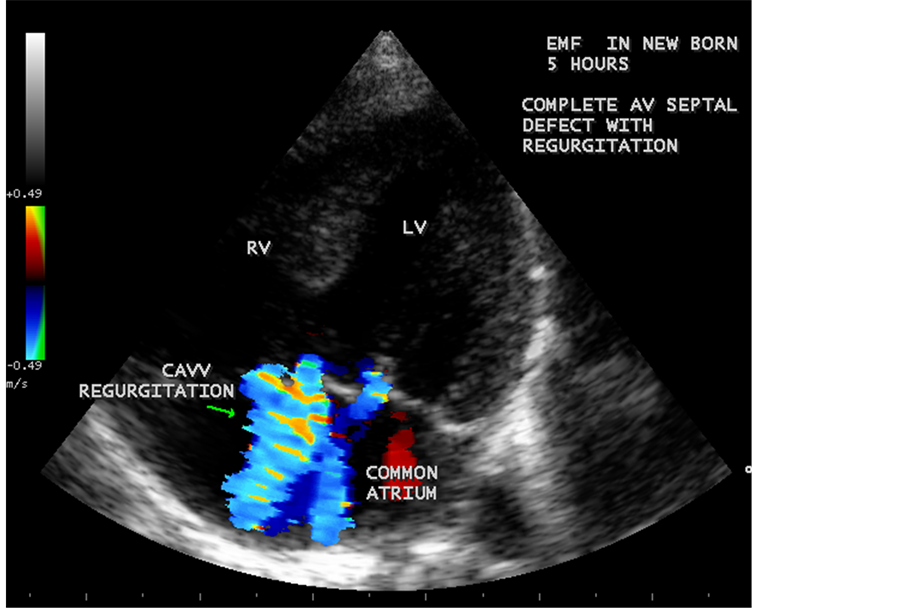

Figure 68. Showing the complete AV septal defect with fibrosis of CAVV (common AV valve) in a new born with EMF.

Figure 72. Showing the CAVV (common AV valve) regurgitation in new born.

RV EMF was detected antenatally in a 22-year-old woman with 8 months amenorrhea as in Figure 67. Endomyocardial fibrosis with left ventricular endocardial calcification and subvalvular fibrosis was detected in a new born with complete AV (atrioventricular) septal defect as shown in Figure 68 to Figure 72. EMF associated with fibrosis of papillary muscle and aneurysmal left ventricle is shown in Figure 74 and Figure 75 in a 56-year-old female. RV EMF associated with right sided pleural effusion, massive ascites and smoke (spontaneous echo contrast) in both ventricles are shown in Figure 76 to Figure 82 in a 42-year-old male. Classical case of RV EMF was shown in Figure 83 and Figure 84 in a 55-year-old male.